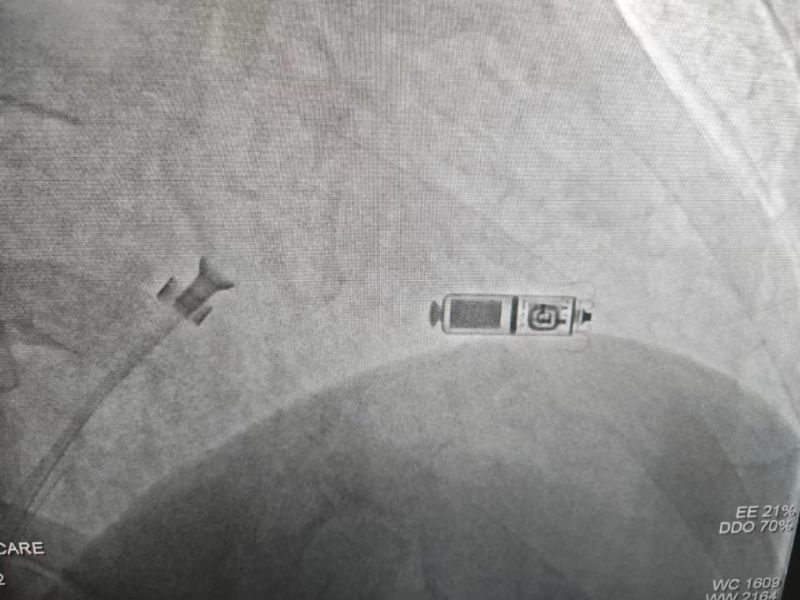

手术过程:经过充分的术前讨论,在延安大学咸阳医院心血管病院吴栋梁院长、刘雄涛副院长的指导与支持下,李阳教授、何克强主治医师、辛浩主治医师与导管室介入团队的共同努力下,经过超声科、心电中心等多学科协作,成功为患者植入双腔无导线永久起搏器,术后第二天患者在起搏器保障下经药物治疗恢复正常的窦性心律。目前患者心脏情况及脑梗均恢复良好,已顺利出院。

科普:Micra无导线起搏器号称“世界最小起搏器”,无需植入心内膜导线,也无需在胸前皮下制作囊袋放置脉冲发生器(起搏器),手术仅需局部麻醉,通过股静脉穿刺,将起搏器经导管植入心腔内,手术时间短,减少出血、血肿及感染风险,术后恢复快,肢体活动不受限,无异物感。

优势:比传统起搏器体积减少93%,体积更小,重量仅2g,类似一颗维生素胶囊;虽体积只有传统起搏器十分之一,但其小小身体储存大能量,续航时间超过12年,整个手术过程平均约30分钟,植入成功率高,术后8-12小时即可下床活动,术后1-2天即可出院;兼容1.5T(特斯拉)/3.0T全身核磁共振扫描。满足患者植入Micra之后疾病的诊断和治疗需求。